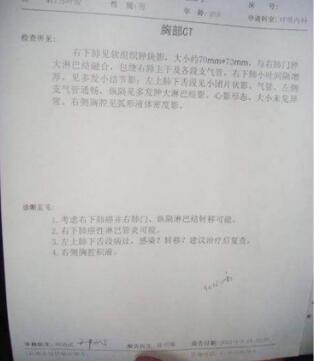

2019年3月份,家住肥西的刘大爷突然出现无故咳嗽,而且伴有痰血,随后到附近医院进行检查。DR检查报告单显示:刘大爷被确诊为肺癌。确诊后,医生建议其住院接受手术切除。

4月16日,由于未能得到及时、有效的治疗,复查结果显示团块状影已经长到70mm✕73mm,这让他意识到已不能再耽搁了。因害怕手术,希望找到其他治疗方法,然而,几乎所有的医生同样给出手术建议。“我一看肿瘤那么大,你说那个创伤面多大多厉害。”刘大爷再次毅然拒绝医生手术建议。